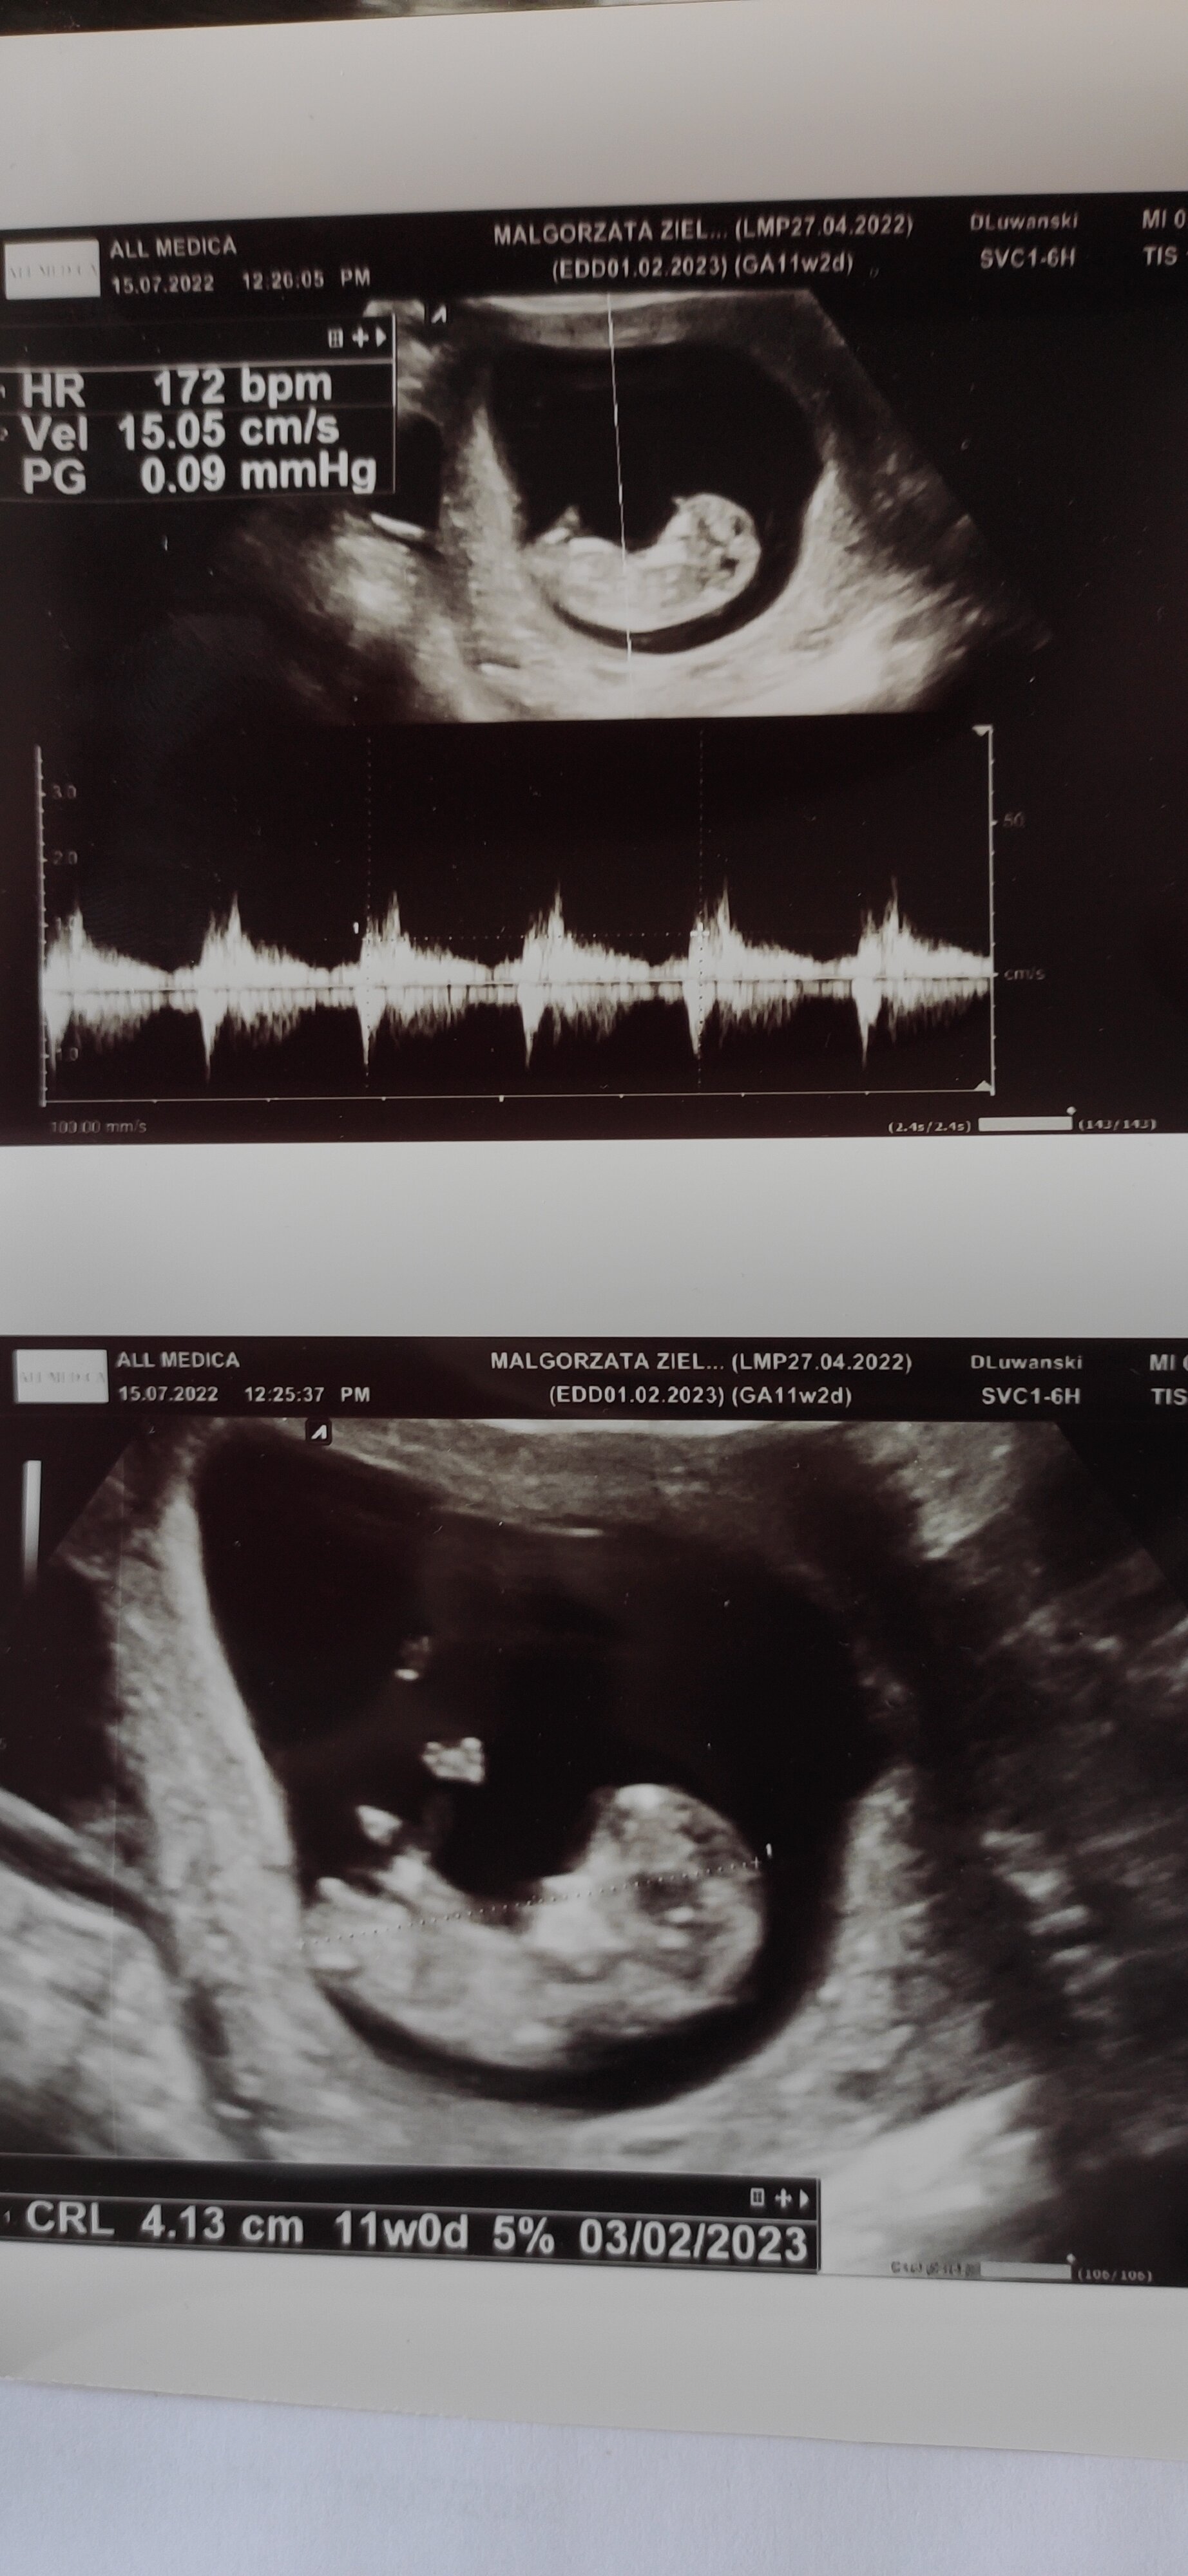

Coś tam się majaczy w pęcherzyku

musisz poczekać, ewentualnie możesz za dzień lub dwa udać się do innego ginekologa. Może być że inny lekarz będzie miał dokładniejsze USG, albo za dwa dni będzie już pięknie wszystko widać, ale może też być puste jajo. Też przez to przechodziłam. W tej ciąży u mnie lekarz nie widział pęcherzyka, wysłał do szpitala z skierowaniem strasząc ciążą pozamaciczną a w szpitalu pytali się ci to za lekarz, bo pęcherzyk pięknie widoczny. Wiele też jest historii że niektóre dziewczyny usłyszały też że puste jajo, postanowiły jeszcze kilka dni poczekać i pokazywał się zarodek. Także wszystko się może zdarzyć. Póki co nie trać nadziei